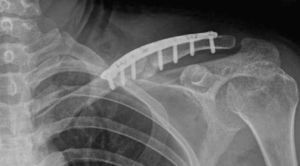

Todos los pacientes fueron intervenidos por el mismo cirujano. Colocados en posición de silla de playa, se practicó un abordaje siguiendo el eje longitudinal de la clavícula. Una vez localizados los extremos de la fractura se realizó el curetaje del foco, la liberación de las partes blandas interpuestas y la reducción temporal de los fragmentos con pinzas reductoras. La fijación definitiva de la clavícula se lleva a cabo con una placa anatómica preconformada colocada siempre en la cara superior (Acumed, Hillsboro, OR®). En 15 de los 34 pacientes (44,1%), en los que había pasado más de tres semanas de la fractura, se aportó sustitutivo óseo (BMX, Synthes® Oberdorf) (fig. 3).

En cuanto a la consolidación se refiere, ésta se consiguió con un tiempo medio de 14 semanas (8-42 semanas). Para la evaluación radiológica de la consolidación de la fractura se observó el paso de puentes óseos entre los fragmentos de fractura (fig. 4). En 7 casos se solicitó además una tomografía computarizada para la confirmar la consolidación.